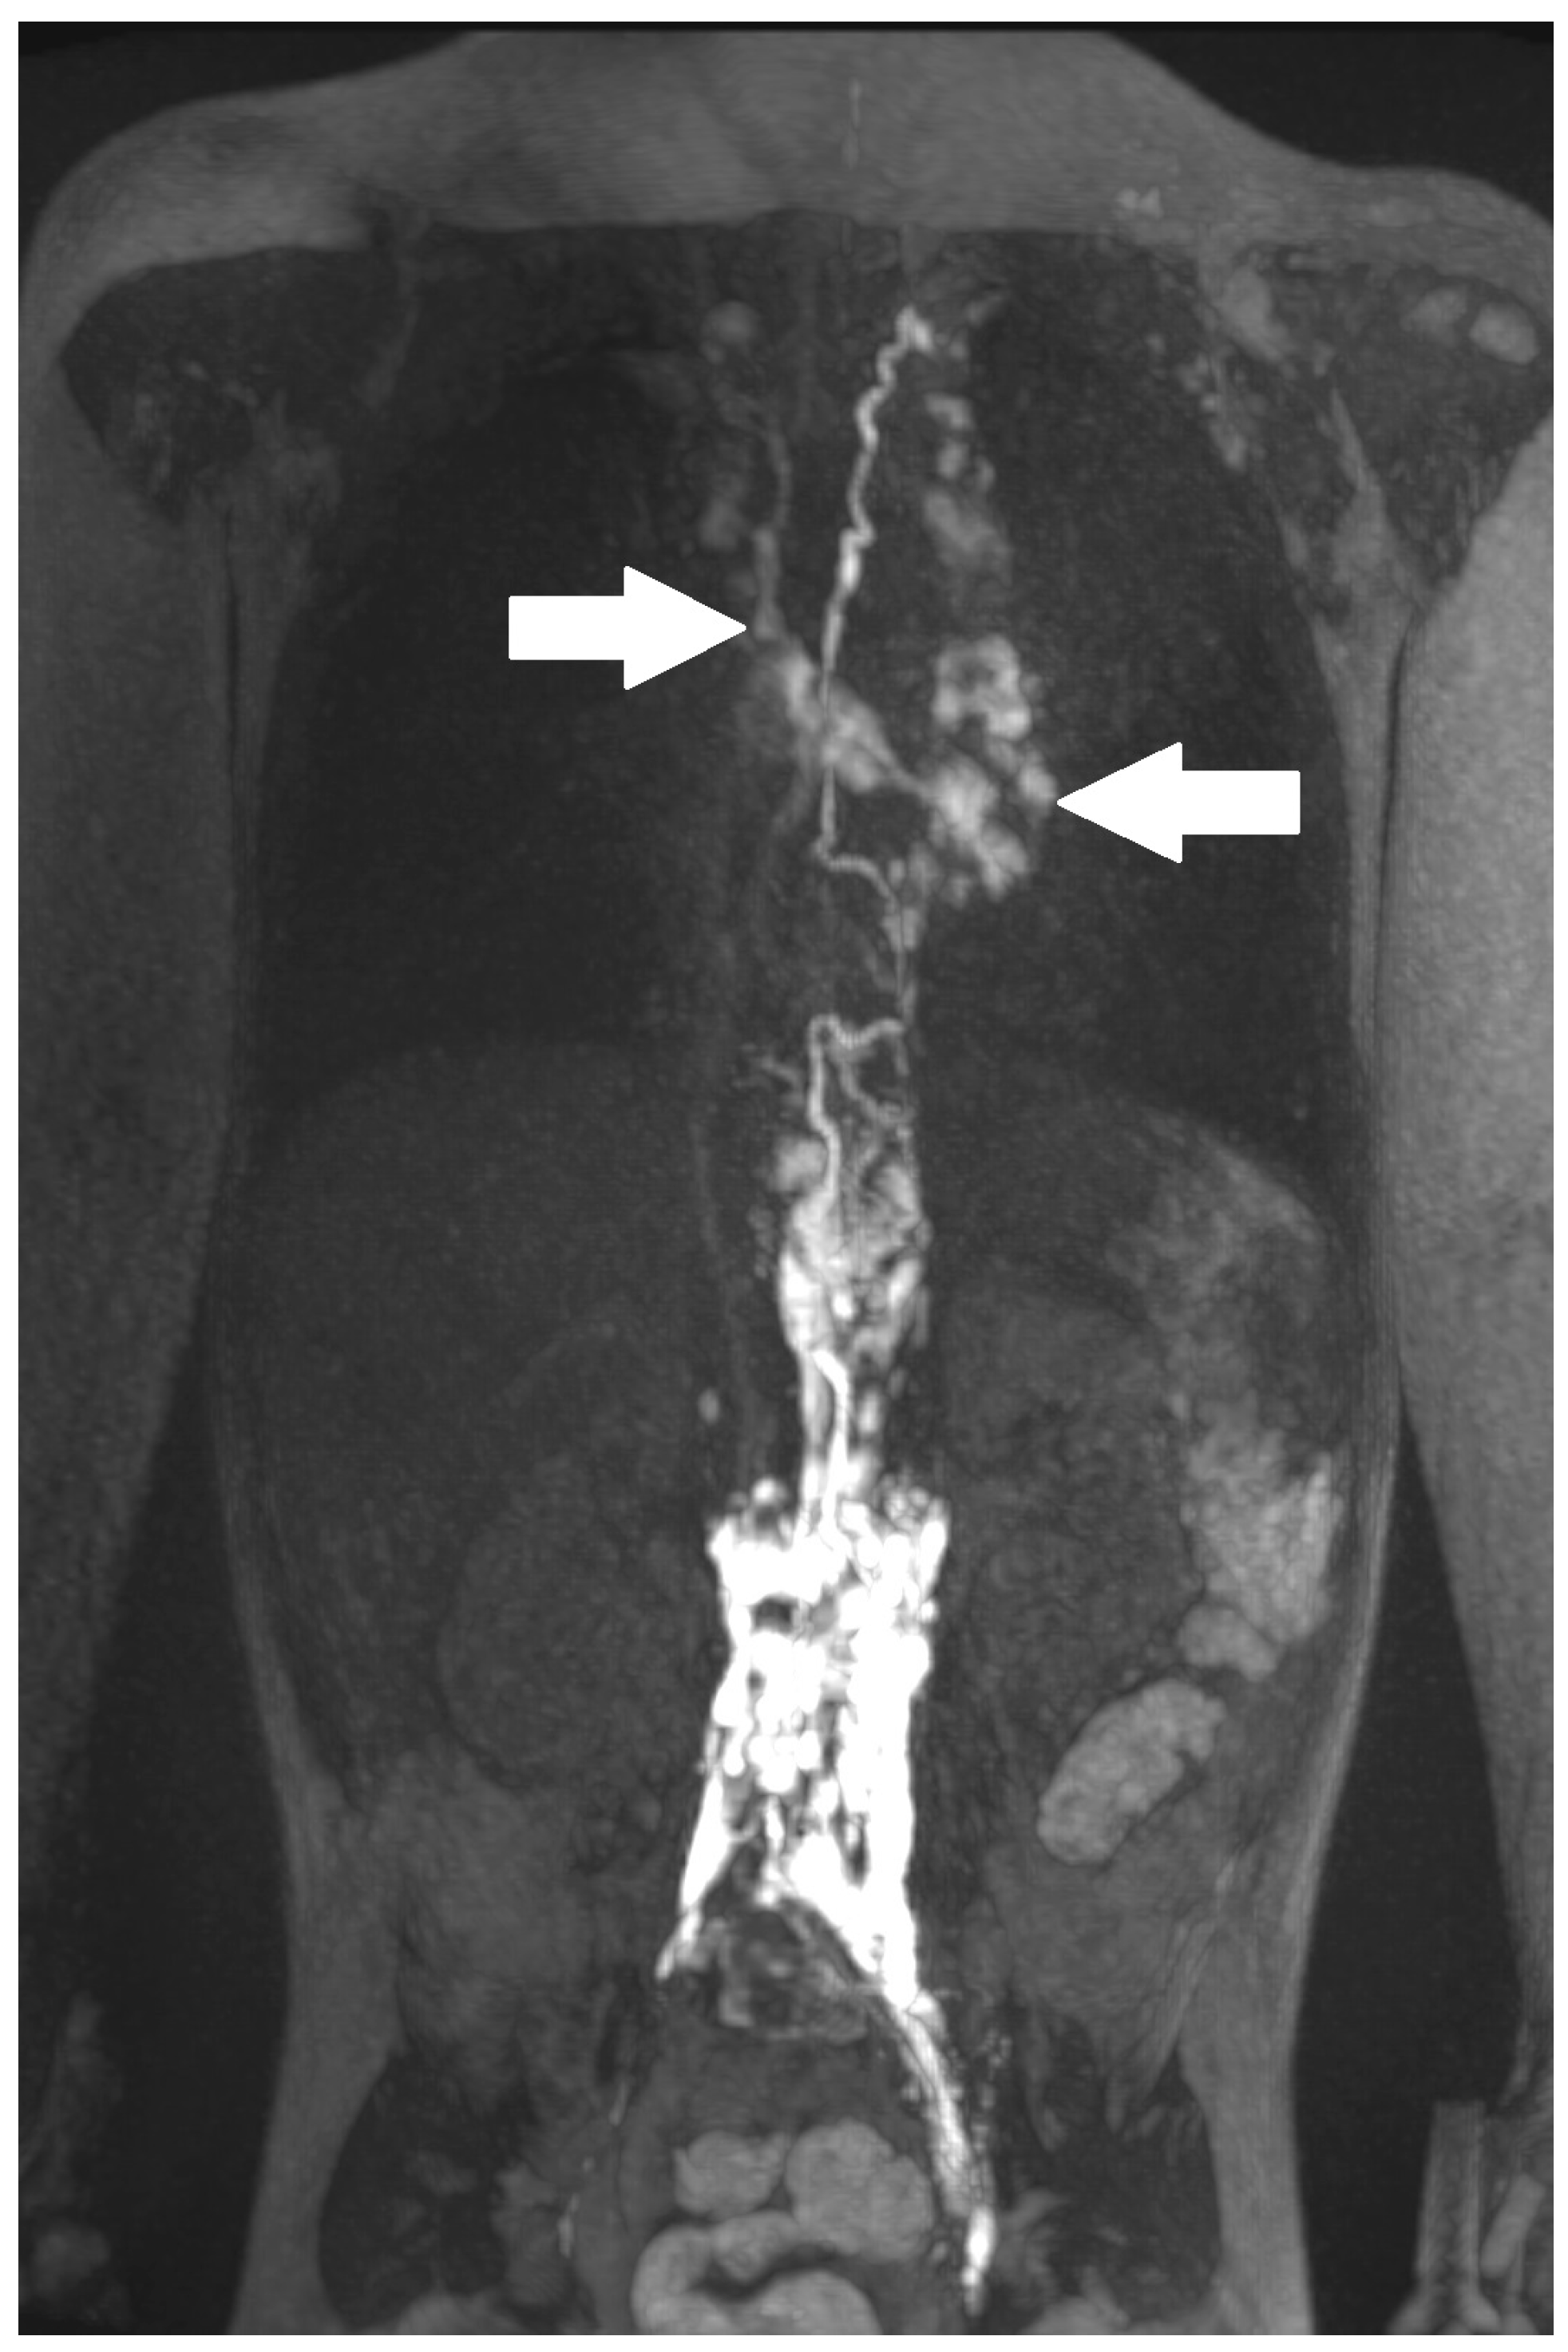

| 1 | 4 | increased signal neck, mediastinum, hilum, perihilar, interstitial lung parenchyma, pleural effusion | abnormal, perfusion to the lung, intercostal flow, dilated lymphatic networks in neck, mediastinum, hilum and perihilar | in the right apical lung | diuretics, sildenafil, non-invasive ventilatory support | lymphatic intervention | Resolution of CT (FU: 10 m, cessation of ventilatory support. |

| 3 | 4 | increased signal neck, mediastinum, hilum, interstitial lung parenchyma, body wall edema, pleural effusion, ascites | abnormal, perfusion to the lung, intercostal flow, dermal backflow, | TV 6–9 bilateral into the lung | diuretics, sildenafil, MCT diet, non-invasive ventilatory support | no | persistent chylothorax, respiratory support |